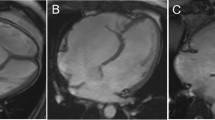

The displacement index was measured in unrepaired patients with EA using the end-diastolic apical four-chamber view. The distance from the insertion of the anterior mitral valve leaflet to the displaced hinge point of the septal leaflet of the TV was measured (Fig. 1A) and indexed to the body surface area. The Celermajer index (CI), the ratio of the RA and aRV area to that of the fRV, left atrium (LA) and LV area, was calculated in unrepaired patients in a four-chamber view at end-diastole (Fig. 1B). The acquired values were classified into four grades: grade 1 (CI < 0.5), grade 2 (CI 0.5 to 0.99), grade 3 (CI 1 to 1.49), and grade 4 (CI > 1.5). [17] Higher grades indicate more severe EA.

Measurement of the displacement index (A). Celermajer index by echocardiography (B). Overview of segmentation of Celermajer index (C) and total right/left volume ratio (D) on CMR. Note that actual ventricular volumes were obtained on a volumetric stack of short-axis slices. CMR cardiac magnetic resonance, fRA functional right atrium, fRV functional right ventricle, d distance, LA left atrium, LV left ventricle

The tricuspid annulus displacement index was calculated as by echocardiography. CI was calculated as previously described by Cieplucha et al. [21] as the ratio of the end-diastolic volume of the RA and aRV to that of the summed end-diastolic volumes of the fRV, LA and LV (Fig. 1C). Total right/left-volume index was determined as proposed by Hösch et al. [22] End-diastolic volumes derived from CMR SSFP cine stacks were used for calculation of this index: (RA + aRV + fRV)/(LA + LV) (Fig. 1D).